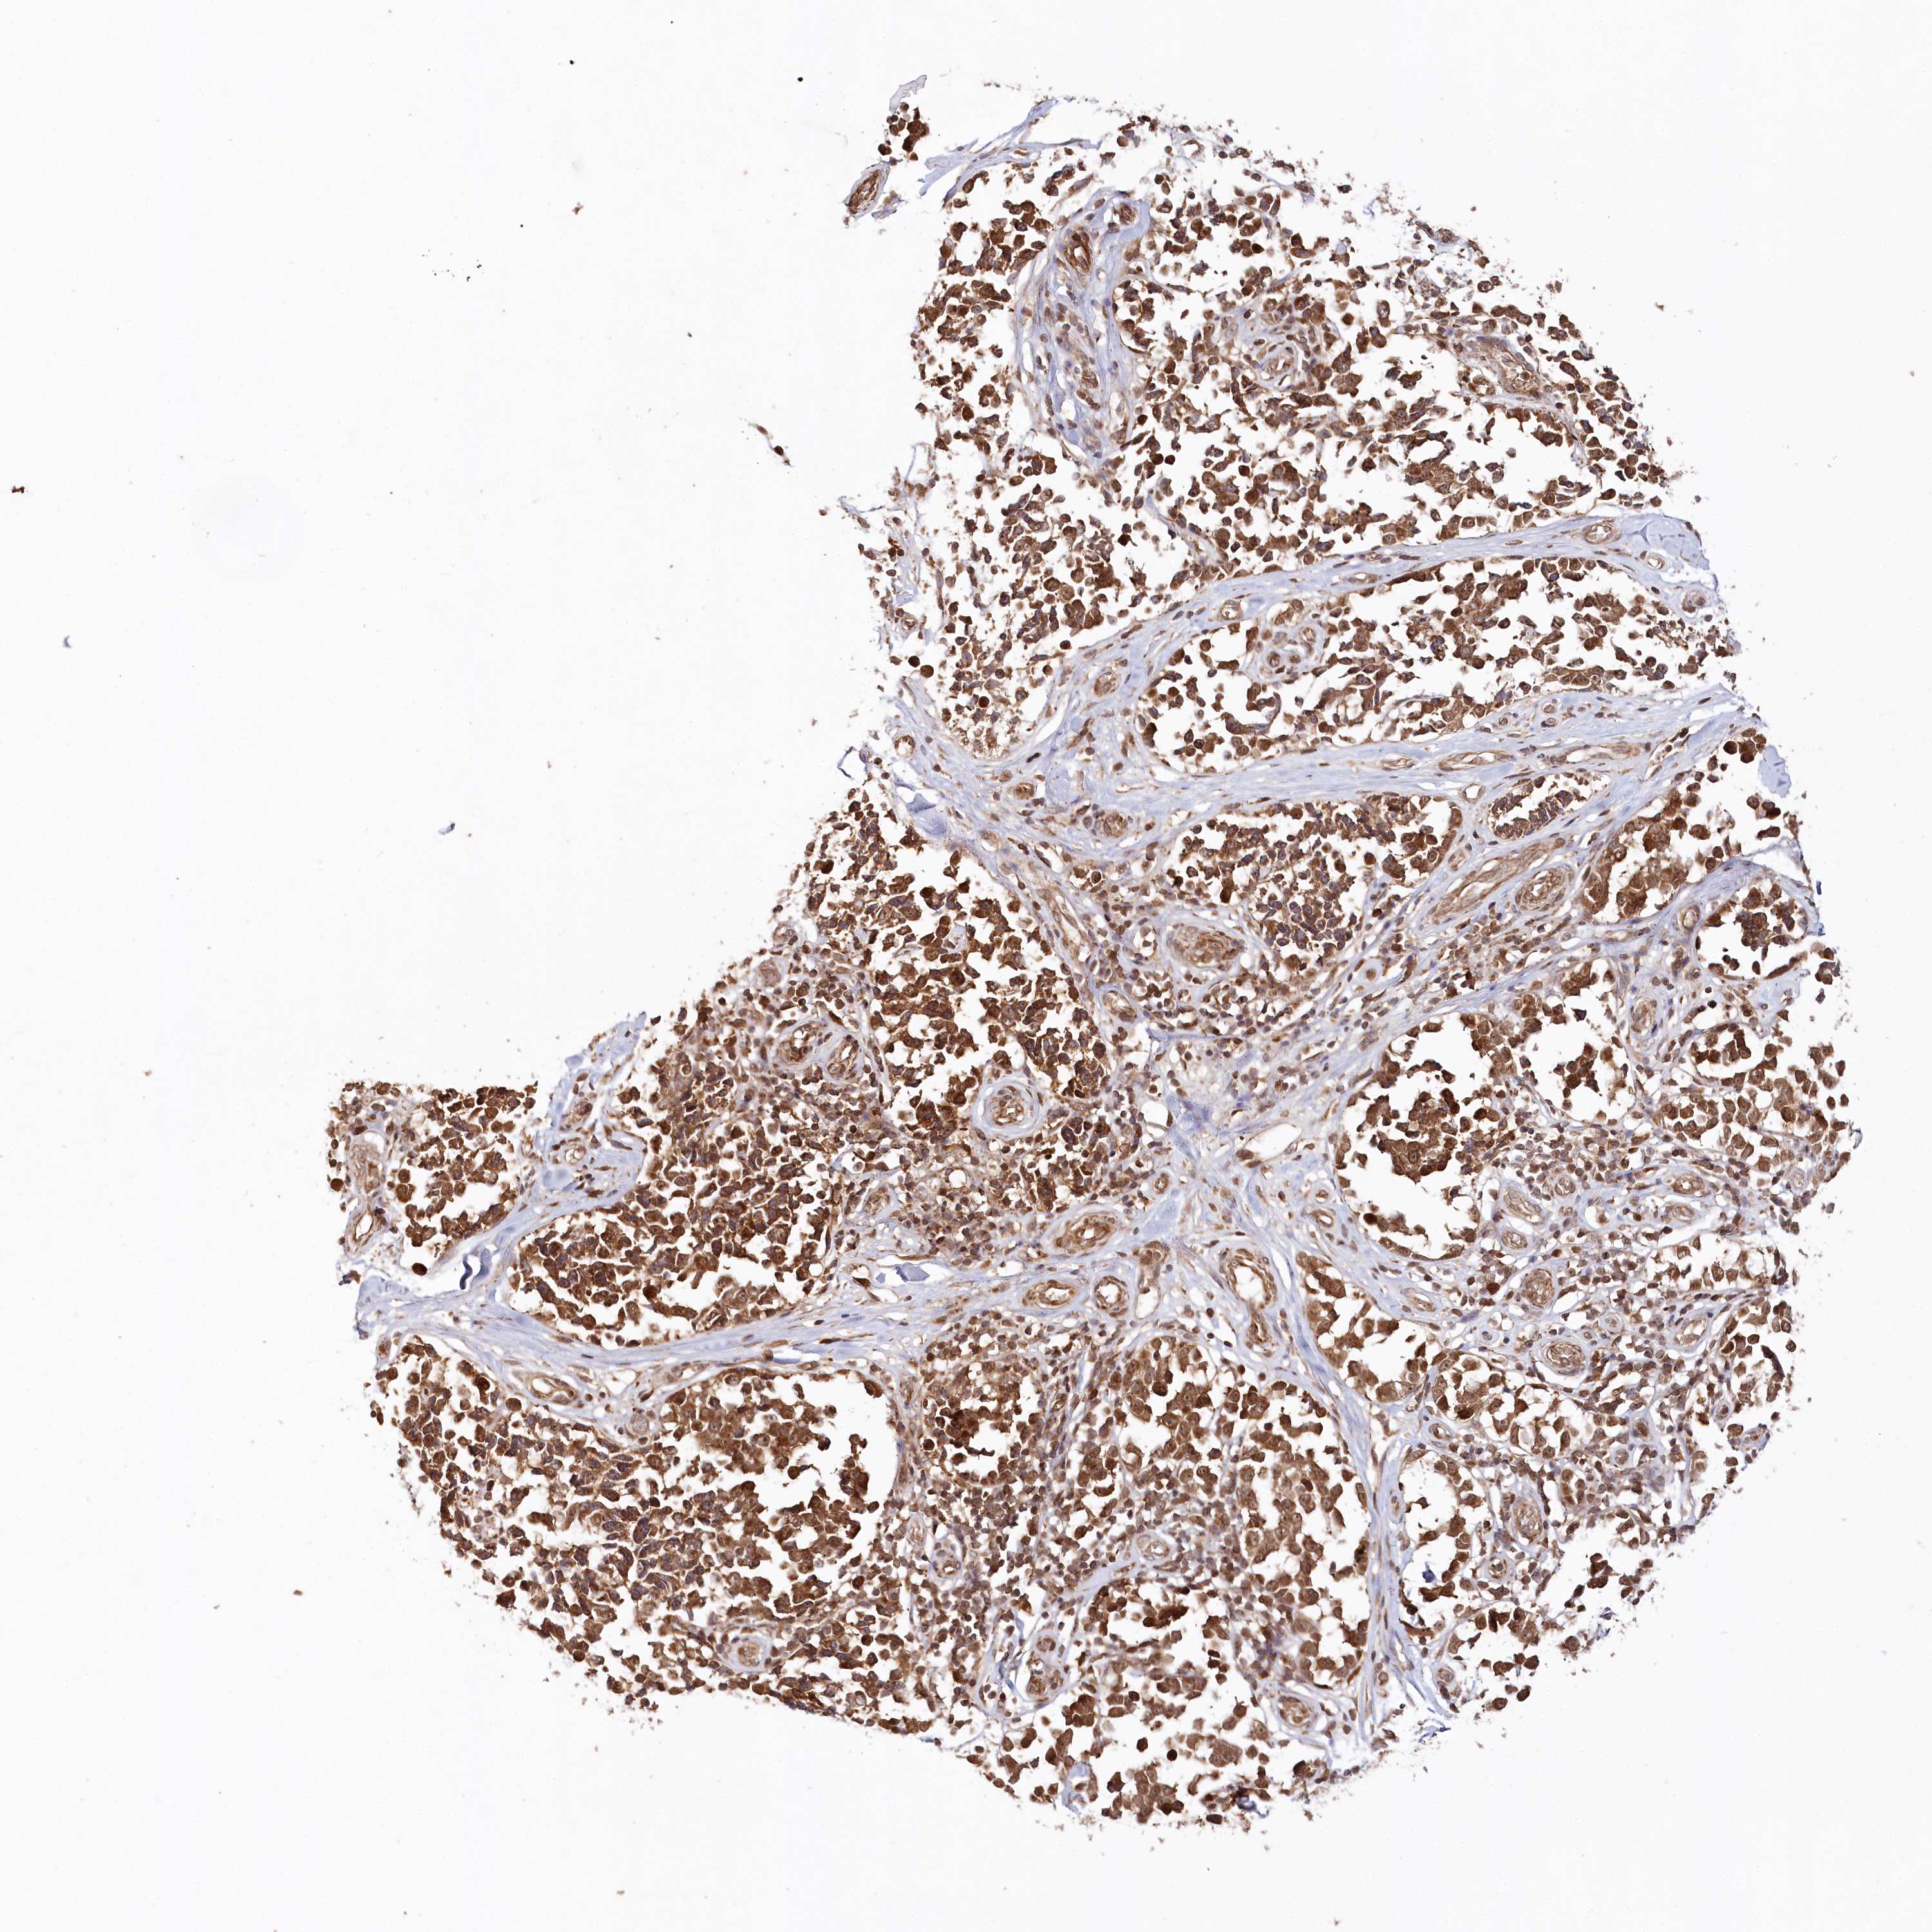

MELANOMA - Protein expressioni

A mouse-over function shows sample information and annotation data. Click on an image to view it in a full screen mode. Samples can be filtered based on level of antibody staining by selecting one or several of the following categories: high, medium, low and not detected. The assay and annotation is described here.

Note that samples used for immunohistochemistry by the Human Protein Atlas do not correspond to samples in the TCGA dataset.

Antibody stainingi

Antibody staining in the annotated cell types in the current human tissue is reported as not detected, low, medium, or high, based on conventional immunohistochemistry profiling in selected tissues. This score is based on the combination of the staining intensity and fraction of stained cells.

Each image is clickable and will lead to virtual microscopy that enables deeper exploration of all samples and also displays staining intensity scores, fraction scores and subcellular localization as well as patient and tissue information for each sample.

Antibody CAB037021

Staining

High

Medium

Low

Not detected

Intensity

Strong

Moderate

Weak

Negative

Quantity

>75%

75%-25%

<25%

None

Location

Nuclear

Cytoplasmic/membranous

Cytoplasmic/membranous,nuclear

Malignant melanoma, Metastatic site